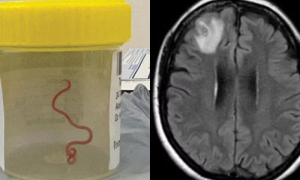

Live Worm Found in Australian Woman’s Brain